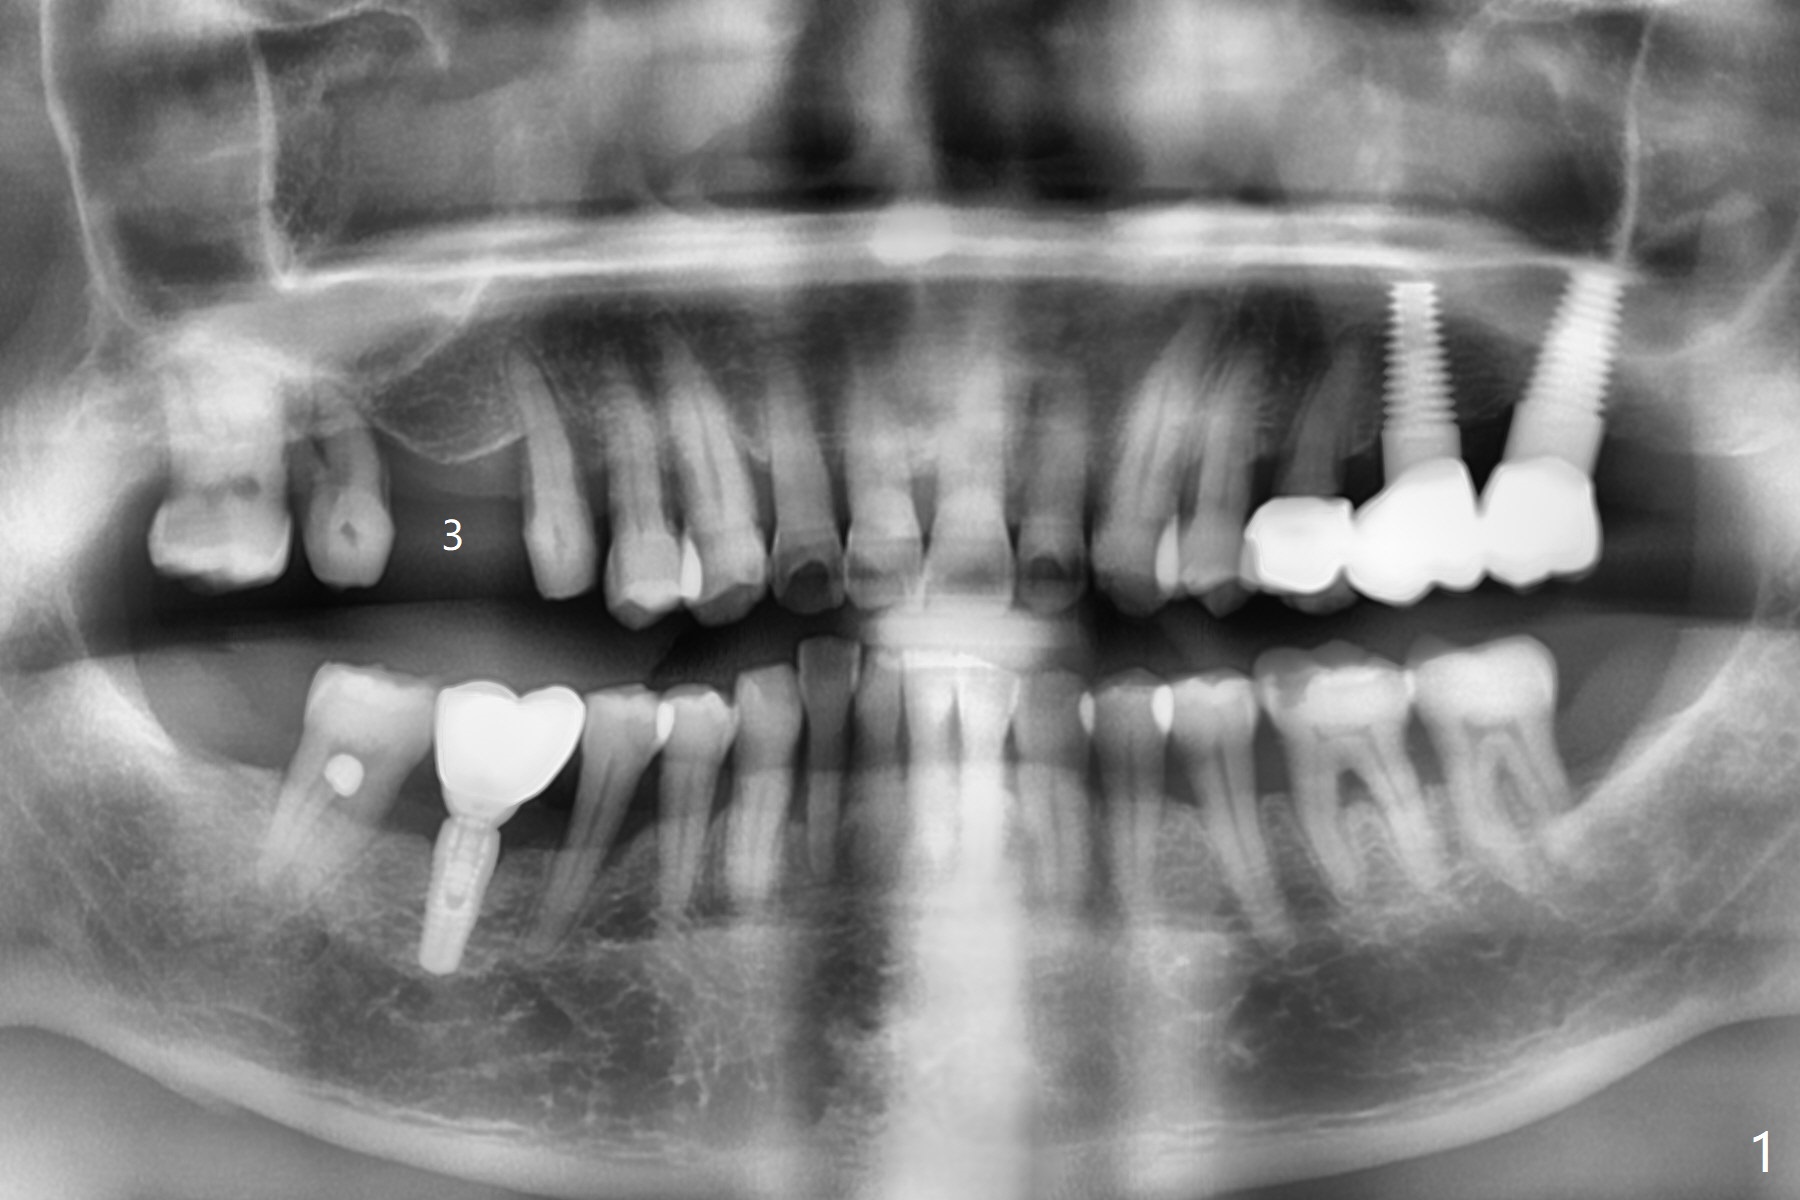

A 64-year-old man has a loose FPD at #2-4. After discussion, he agrees to have it removed for implant at #3 (Fig.1). In fact the bone loss at #2 is severe (Fig.2, as compared to #4 (Fig.3)). When the implant osteointegrates (Fig.4), make single unit crowns and let the patient decide whether the tooth #2 is salvageable or not.